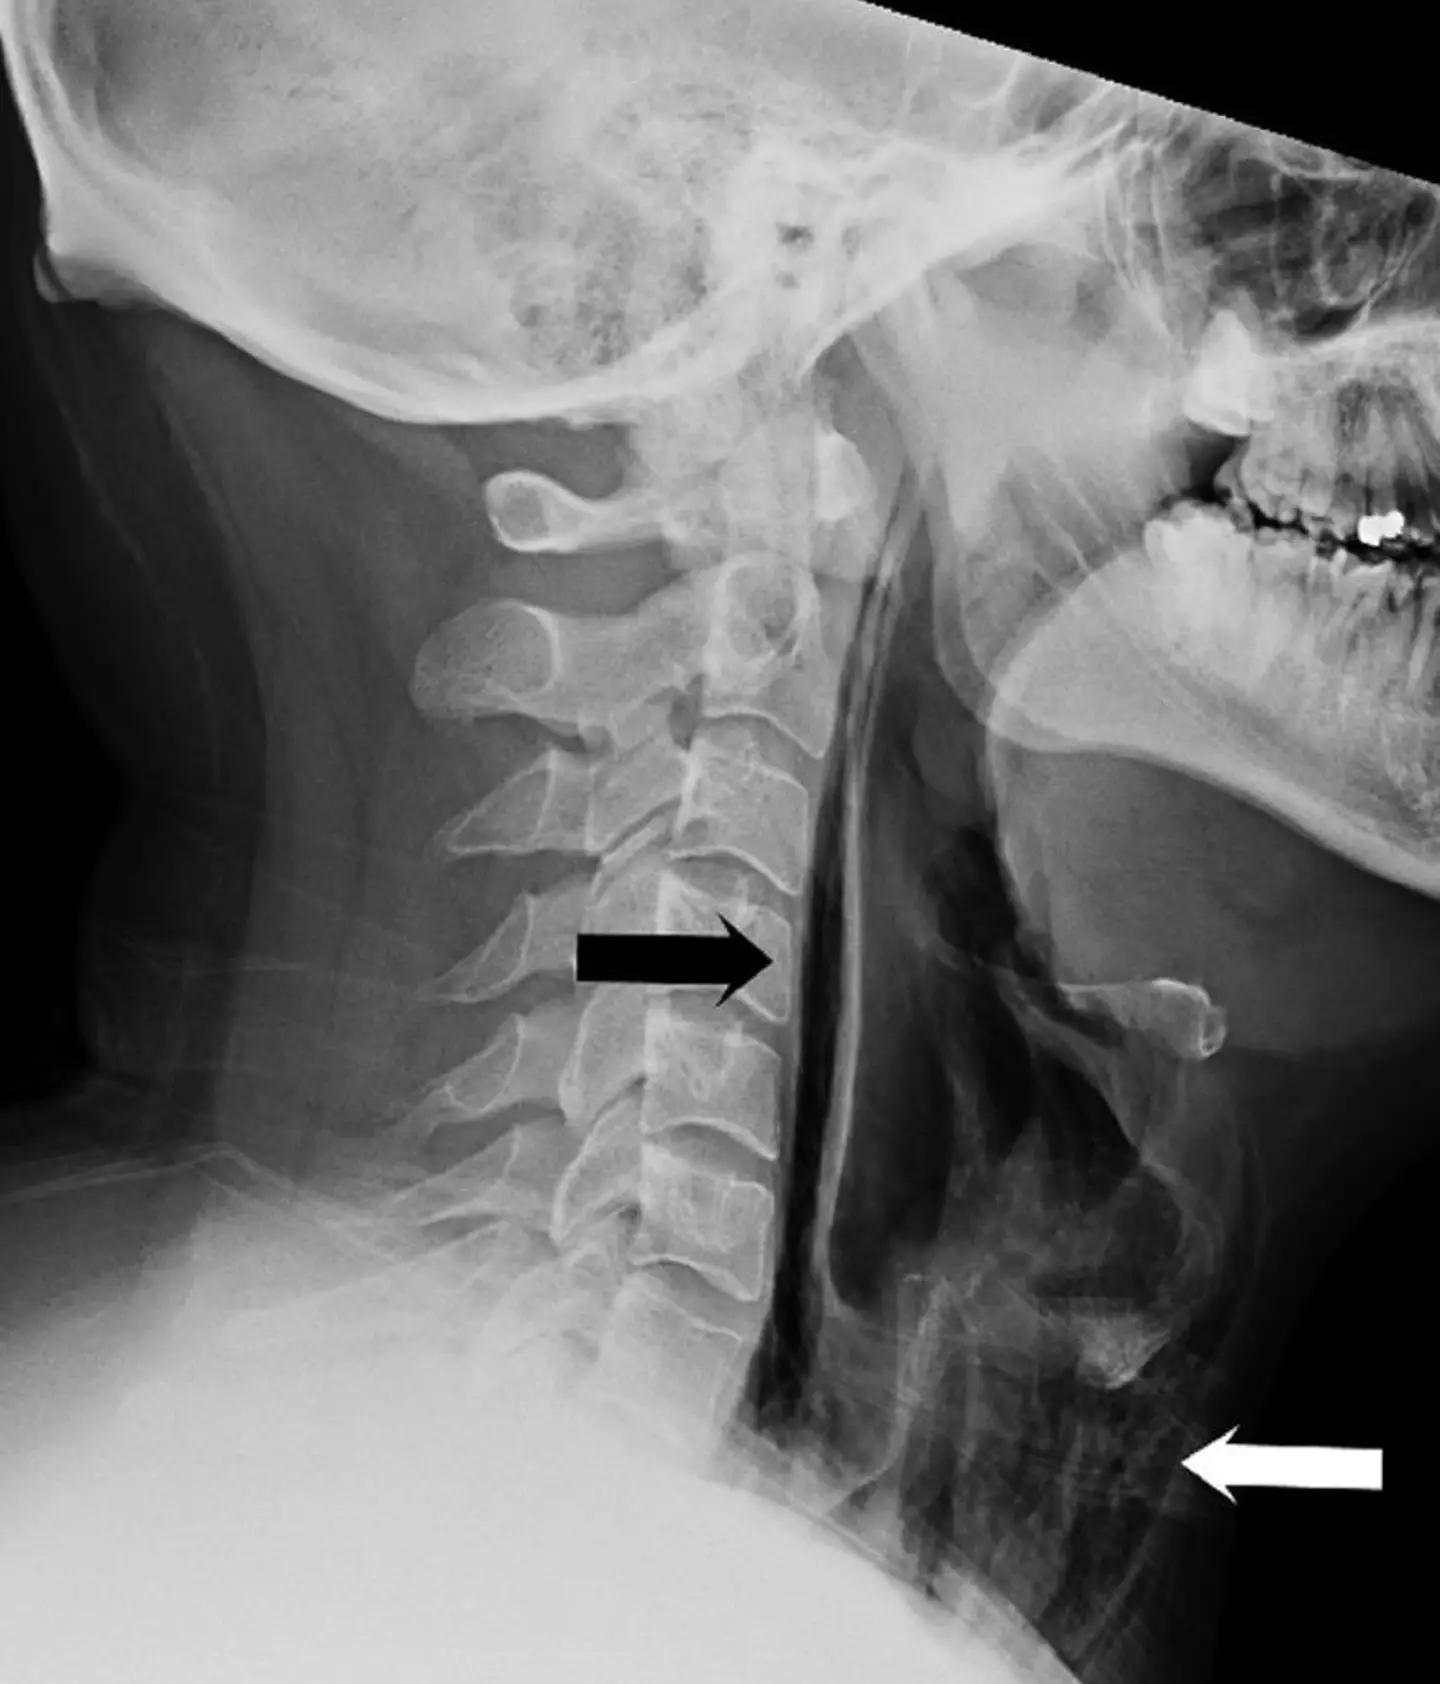

Upon a physical examination, health professionals found 'swelling and tenderness' in his neck with an X-ray later revealing that 'streaks of air' had become trapped in parts of the man's throat tissue.

Lovely image - I know.

These pockets of trapped air effectively meant the man had ruptured his own throat.

The authors added that it was the type of injury that usually results from trauma, surgery, or infection.